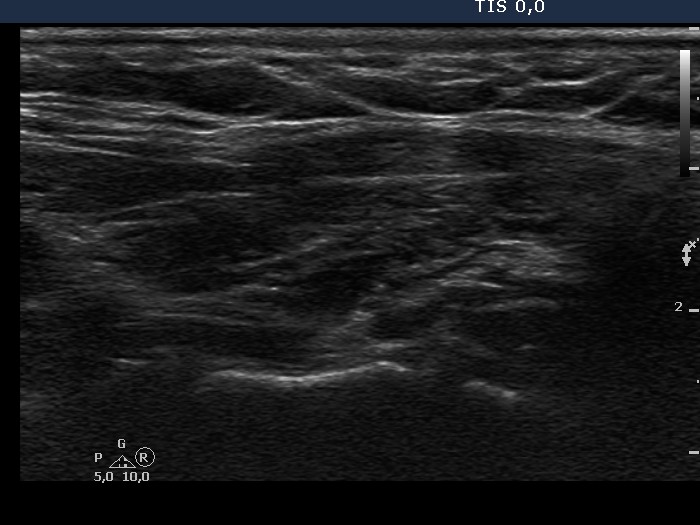

Chronic lymphocytic thyroiditis - Case 36. (ultrasonographic picture 5)

Left lobe, longitudinal scan. Multiple hypoechogenic areas are seen.